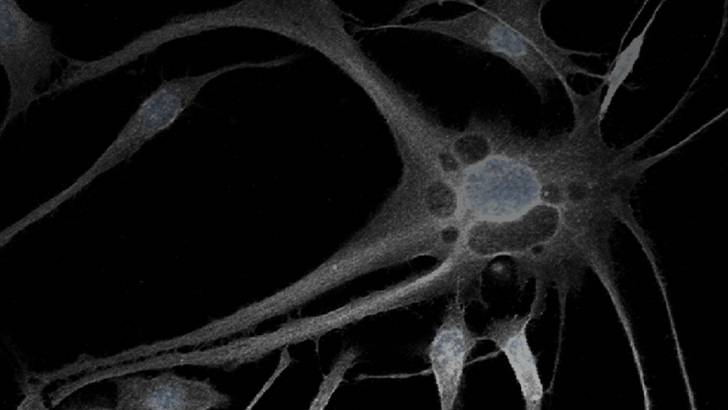

That’s a really good question. The term “eloquent” was adopted, really by neurosurgeons, really to indicate the parts of the brain that are directly involved in neurologic function, that are critical to that function – where, if we were to cause injury in those areas, patients could have very disabling neurologic deficits. And so these are considered essential for very basic neurologic functions. Other parts of the brain – the non-eloquent parts of the brain, as we now refer to it – used to be referred to as “silent.” We know the other parts of the brain are not silent, so now we refer to them as non-eloquent, really indicating that they have more subtle function, and perhaps function that may be duplicated in other areas, so injury to those areas would not be necessarily as dramatic-appearing as if it were to occur in eloquent areas. So, typically when we think about eloquent areas, we think about the sensory-motor cortex, the language cortex, visual cortex, you know, thalamus with our sensory function, and our motor function with the internal capsule and basal ganglia. Those are the main areas that we think of as eloquent areas.

Well, thank you Dr. Sherman. Indeed, they should do a functional MRI, of course. We have our multi-disciplinary team of neuropsychologists that help us understand how this potential tumor is having an effect on those eloquent and subtle functions that Dr. Sherman was alluding to. So we do not only functional, in regards to language, understanding of language, production of language, vision, memory, but also we look at the deep white matter connections that allow those areas of the brain to function as a unit. So, in essence, we try to understand, “How is this tumor affecting the quality of life of our patient, in addition to the language or the motor function?” And we are beginning to understand how will we go into the operating room to disconnect those areas, take a tumor out, and ideally leave the patient intact.